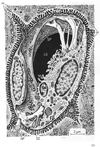

肝臓【かんぞう】 Organ located in the upper right side of the abdomen in the hypochondrium. Its inferior border runs from the upper left to the lower right through the epigastric region. In healthy subjects its border does not reach below the costal margin. It moves with respiration and is thus palpable.(肝臓は身体内の最大の腺であり多様な機能を営むが、それを①胆汁の生産と分泌(腸管内へ)を行う、②炭水化物、脂肪、蛋白の代謝活動、③胃腸管から血液中に進入した最近や異物を細くする、とう3点に要約することができる。(1)位置と形状:肝臓は右上腹部ある巨大な消化腺で、重さは男で1,400g、女で1,200gほどある。色は暗赤褐色で、これは充満する血液によるものである。肝臓の表面が平滑で光沢に富むのは腹膜(の臓側葉)におおわれているからである。肝臓の上面は横隔膜の下面に接して丸く膨らみ、横隔面と呼ばれる。横隔膜上の心臓に対応して、浅い心圧痕をみる。からだの正中にほぼ相当して、横隔面を大きい右半と小さい左半に二分する肝鎌状間膜が走る。これは肝臓の表面を被う腹膜が左右から翻転しながら寄り合い、その間に線維性の結合組織をいれるもので、肝臓を横隔膜から吊り下げる役をしている。このようにして横隔膜と肝臓は平滑な腹膜で自由に滑り動くようになっているが、後部のせまい領域では、両者が線維性結合組織によって密着して活動性に欠ける。肝臓表面のこの領域を無漿膜野(裸の領域Area nuda--腹膜に包まれていない--の意)という。無漿膜野は前方へ細く張り出して肝鎌状間膜につづき、左右へ細く伸びて左三角間膜と右三角間膜になる。左三角間膜の端は、肝臓の左上端を横隔膜につなぐ索をなして線維付属(Appendix fibrosa hepatis)とよばれる。肝臓の上面と下面の境界は前方でうすくするどい縁をなし、下縁(または前縁)とよばれる。上腹部を斜め右下方へ走る一線をなし、触診することができる。これと右肋骨弓の交点に胆嚢の底が腹壁直下に頭を出している。下縁の正中部には肝円索切痕とよぶ切れこみがあって、肝鎌状間膜をはさんでいる。肝臓の下面は上腹部の内臓に面するので、臓側面とよばれる。ここには矢状方向に走る2条のくぼみと、それを横に結ぶくぼみがHの字をなしている。Hの左縦線は前方の半分が肝円索をいえる肝円索裂、後方の半分が静脈管索をいれる静脈管索裂である。Hの右の縦線には前方に、胆嚢の上面をおさめる胆嚢窩があり、後方に大静脈をおさめる大静脈溝がある。H字の横線に当たる溝は肝門で、門脈、固有肝動脈、肝管のほか多数のリンパ管と若干の神経が通っている。肝鎌状間膜、肝円索裂、静脈管索裂によって、肝臓は大きい右葉と小さい左葉に分けられる。肝臓の臓側面では、右葉(広義)が胆嚢窩、大静脈溝、肝門によって狭義の右葉、中央前方の方形葉、中央後方の尾状葉に分けられる。尾状葉は全科法へ乳頭突起を出し、前右方へ、肝門の後縁に沿って尾状突起を出す。乳頭突起に対峙して左葉から小綱隆起が張り出し、両者の間に小綱をはさむ。(2)肝臓の構築:肝臓の表面は大部分腹膜をかぶり、その下に線維性の結合組織がある。この結合組織は大血管とともに肝臓内に侵入し、血管周囲線維鞘をつくる。ギリソン鞘(Glisson's sheath)ともよばれる。肝臓の実質は径1mm前後の短六(ないし五)角柱の肝小葉を構造単位として成り立っているが、肝門からはいる肝固有動脈と門脈の枝はグリソン鞘を伴って、この肝小葉の稜線(三つの肝小葉の合するところ)に沿って走るこの動静脈を小葉間動・静脈とよぶ。肝小葉の角柱の中心を貫いて中心静脈という太い毛細血管が走り、その周囲に肝細胞の板が放射状に配列する。肝細胞板(hepatic cell plates)は分岐し、吻合し、あなをもち、すきまに洞様毛細血管(sinusoidal capillaries)をいれている。小葉間動静脈の枝は小葉の洞様毛細血管に注ぎ、中心静脈から、小葉下静脈(Vena sublobularis)とよばれる小静脈を経て下大静脈へと流れていく。肝細胞板の中に、肝細胞のあいだを縫って走る細管系が毛細胆管(bile capillary)であって、肝細胞の産生する胆汁を運ぶものである。毛細胆管は肝小葉のへりで小葉間胆管とよばれる小導管に注ぎ、グリソン鞘の中を合流しつつ肝門へ向かう。(3)肝臓と血管:肝臓は門脈の番人というべき器官である。すなわち消化管から送られてくる血液中に余分の糖分があればグリコゲンとして貯え、有害物質があれば分解、解毒する。脾臓から送られる破壊血液のヘモグロビンをビリルビンに変えて胆汁中に排泄する。門間区によって運ばれてくる膵臓のホルモンは、肝細胞でのグリコゲンの産生とブドウ糖への分解を調節する。しかし、門脈血は酸素に乏しい静脈血であるから、肝臓は動脈血を固有動脈にあおがねばならない。胎生期においては、臍から前腹壁を上行して肝臓の下面に達する臍静脈(Vena umbilicalis)が、肝門で門脈と合して、そのまま肝臓の下面を後方へ走り、下大静脈に注ぐ。細静脈と下大静脈のこの短絡路を静脈管またはアランチウス(Arantius)の管と称する。生後、胎生期の循環路は閉鎖し、結合組織索として残る。臍静脈の遺残が肝円索、静脈管の遺残が静脈管索である。 (解剖学事典 朝倉書店より引用) 肝臓の生理 肝臓は重要な機能を営む器官であり、肝臓を楔状すると12時間前後で低血糖で死亡するといわれている(動物実験では70%の肝切除でも数週で機能が正常になるといわれている)。)